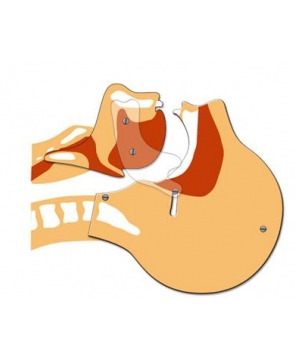

Modèle de tête articulée pour formations de secourisme

Outil pédagogique indispensable lors des formations de secourisme pour visualisation libération des voies aériennes.

La tête articulée représente une coupe de tête de profil.

Permet une schématisation précise des voies respiratoires.

Pour une formation efficace des gestes de secours à adopter pour la pratique de la respiration artifcielle.

– En plexiglas.

– Sans latex.

Dimensions de la plaque: largeur 24 x Hauteur 33 cm.

Dimensions de la tête: largeur 21,5 x Hauteur 31 cm.

Poids: 450 gr.

Garantie 1 an.